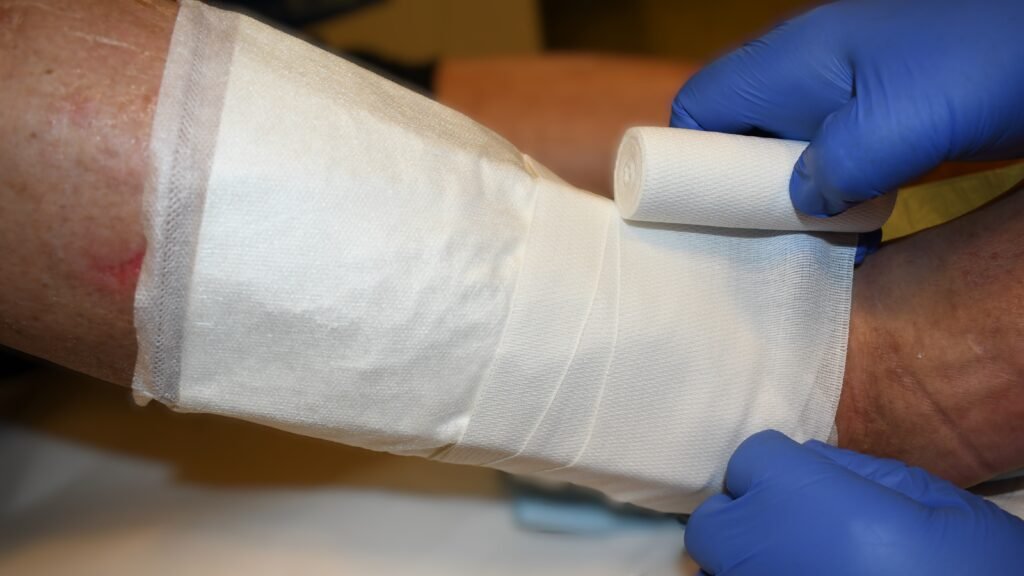

Kompressionsverbände -Binden – Zinkleim –

Zusätzliche Fotos ![]() 2

2